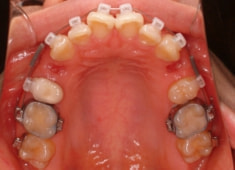

治療後(1年9ヶ月後)